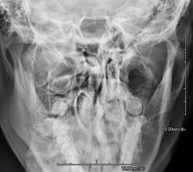

- RX Cráneo

Técnica mediante la cual, utilizando rayos X, se obtienen imágenes del cráneo para su estudio. Indicaciones: traumatismo, cierre precoz de suturas craneales. - RX Senos Paranasales

Técnica mediante la cual, utilizando rayos X, se obtienen imágenes de los senos paranasales para su estudio. Indicaciones: dificultad respiratoria nasal, tos crónica, cefalea, mucosidad. - RX ATM (Articulación Temporo-Mandibular)

- Paranasal Sinuses X-ray

This technique uses X-ray rendered imaging for examining the paranasal sinuses. Indicated for: headache, chronic cough.